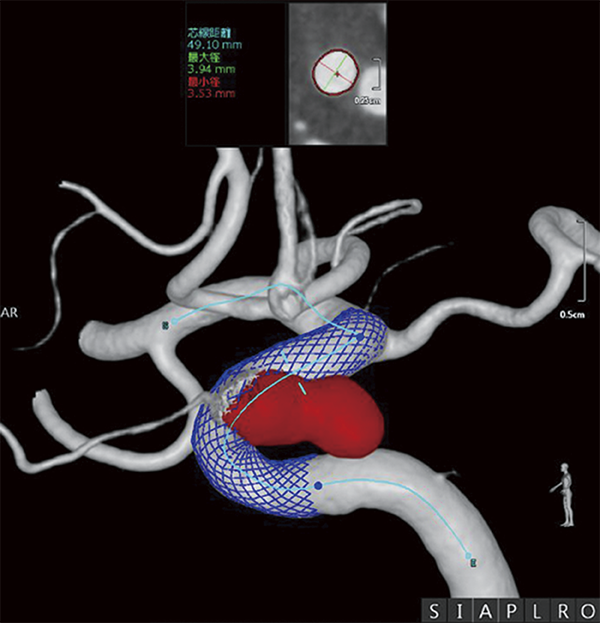

Пацієнт надійшов із нерозірваною аневризмою правої внутрішньої сонної артерії (максимальний діаметр 11,6 мм) і отримав лікування ФД. Зображення 3D-DSA використовувалося для визначення WA (робочого кута), а інструмент підтримки CAA (cerebral aneurysm analysis) використовувався для вимірювання діаметра материнської судини (4,26 мм × 4,02 мм на проксимальному кінці, 5,34 мм × 5,0 мм у середній точці та 3,71 мм × 3,57 мм на дистальному кінці, із зоною посадки 21 мм) (мал. 4).

Малюнок 4: Симуляція CAA розміщення перемикача потоку (FD) (червоний: аневризма, синій: FD).